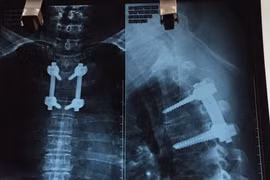

Ngày 21-8, Bệnh viện K Trung ương cho biết, các bác sĩ của bệnh viện vừa phẫu thuật cắt thành công khối u khổng lồ ở tủy sống và lồng ngực rất hiếm gặp cho một nữ bệnh nhân 61 tuổi ở Quảng Ninh.